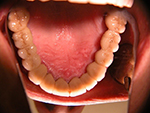

Die folgenden Patientenfälle sollen Ihnen einen Einblick in die Möglichkeiten der modernen Implantation geben.

Komplett-Implantation: